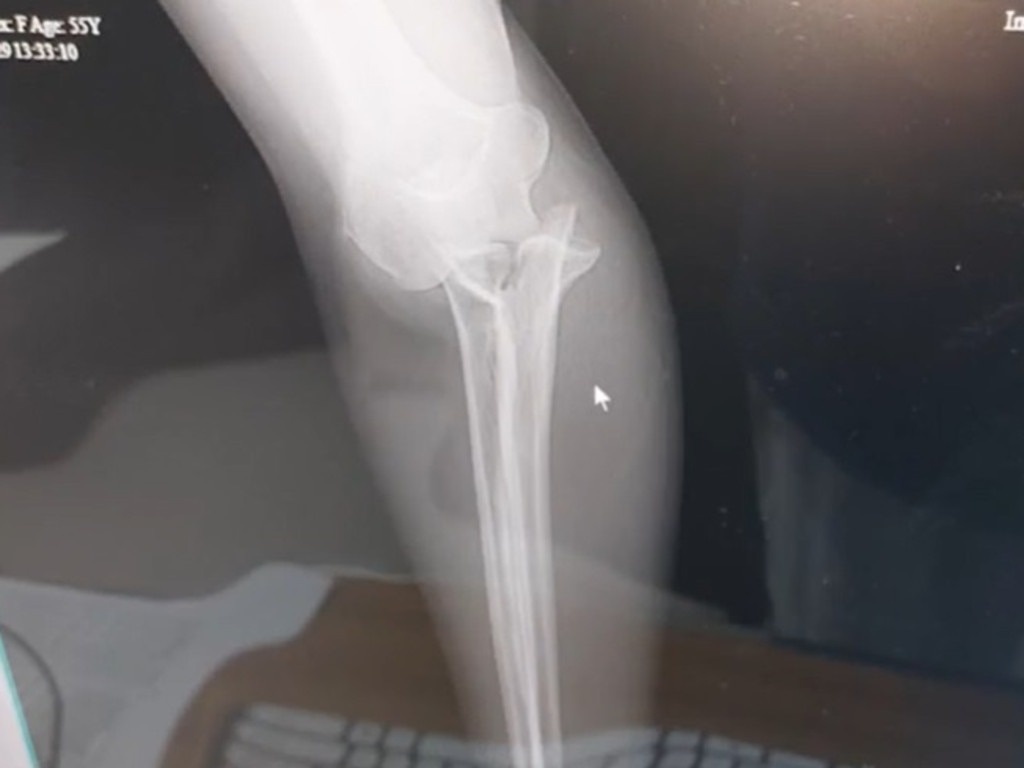

Phim chụp X-quang cánh tay của Beth Bogar sau khi bị hút vào miệng voi cắn. Ảnh: WMUR.

"Tay tôi bị dập nát, bên trong đó là rất nhiều nẹp và đinh vít để cố định phần tổn thương", cô nói.